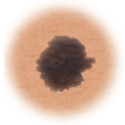

Moles (nevi)

Small skin marks caused by pigment-producing cells in the skin. Moles can be flat or raised, smooth or rough, and some contain hair. Most moles are dark brown or black, but some are skin-colored or yellowish. Moles can change over time and often respond to hormonal changes.

Most moles are benign and no treatment is needed. Some benign moles may develop into skin cancer (melanoma). See below for signs.

Distinguishing benign moles from melanoma

Certain moles are at higher risk of changing into malignant melanoma, a form of skin cancer. Large moles that are present at birth and atypical moles have a greater chance of becoming cancerous. Finding cancerous skin growths early is important because that’s when treatment is most likely to be effective. Removing the melanoma through surgery seems to work best as the treatment. When a melanoma is diagnosed early, surgery usually removes all the cancer.

Normal mole.

Use this ABCDE chart below to help you see changes in your moles at the earliest stages. The warning signs include: